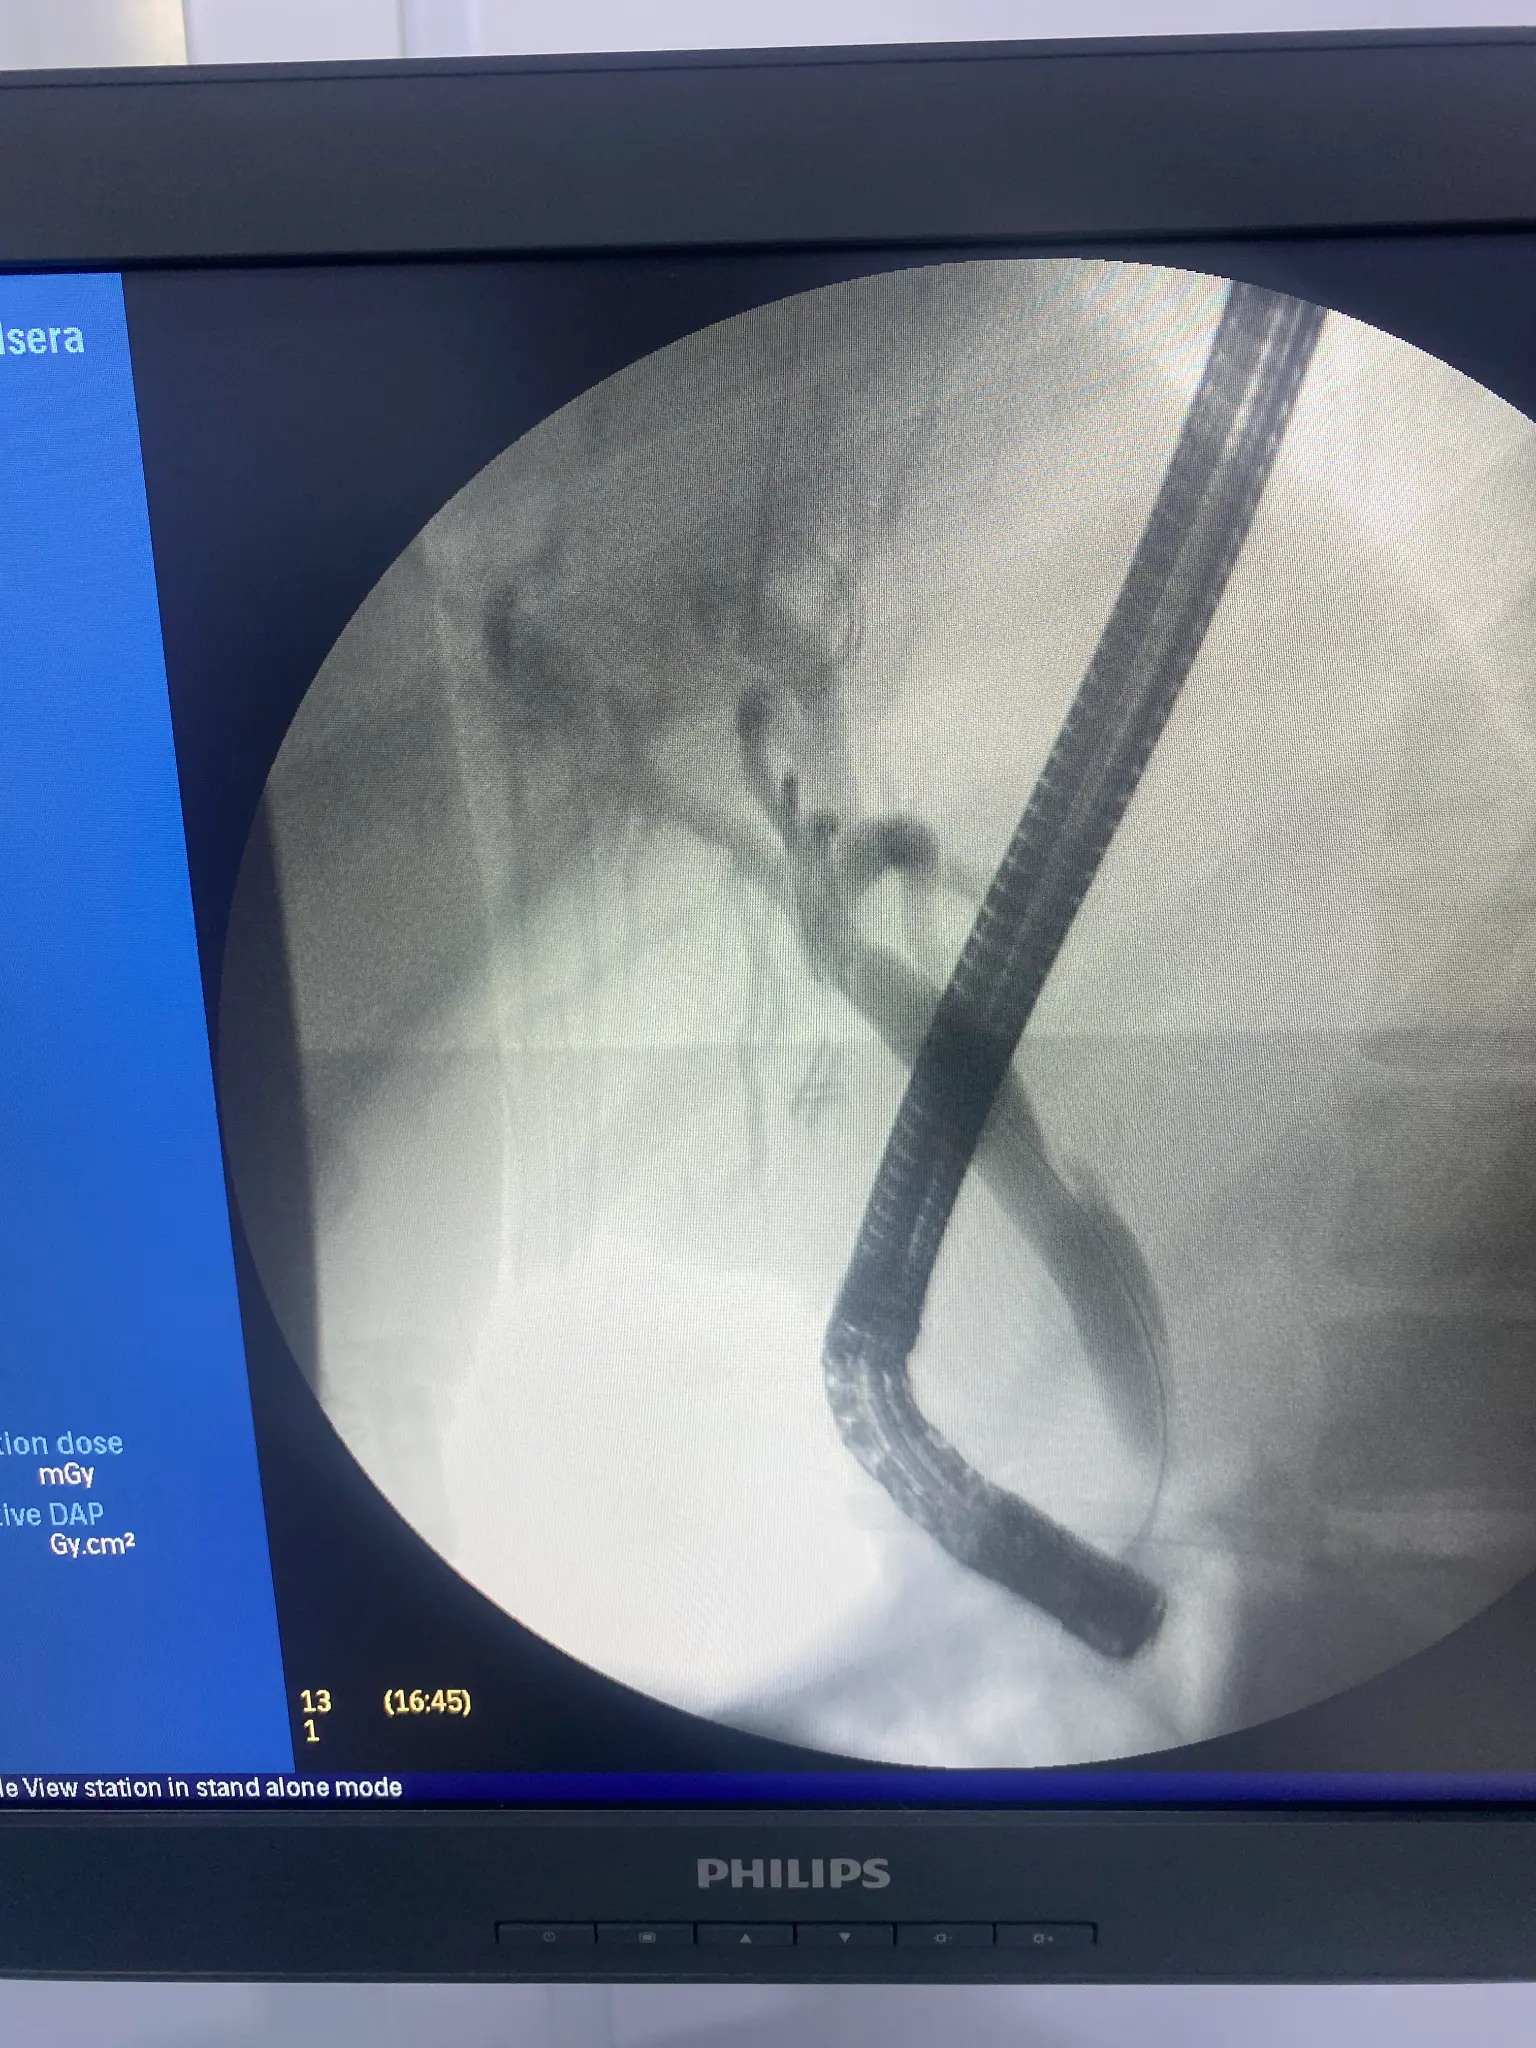

ERCP Intervention Photos

Placement of plastic or metal stents to keep bile ducts open when narrowed by tumors, strictures, or inflammation. Stents restore bile flow and relieve jaundice.

Stretching of bile duct strictures using inflatable balloons to improve drainage. This technique is useful for benign strictures and post-surgical narrowing.